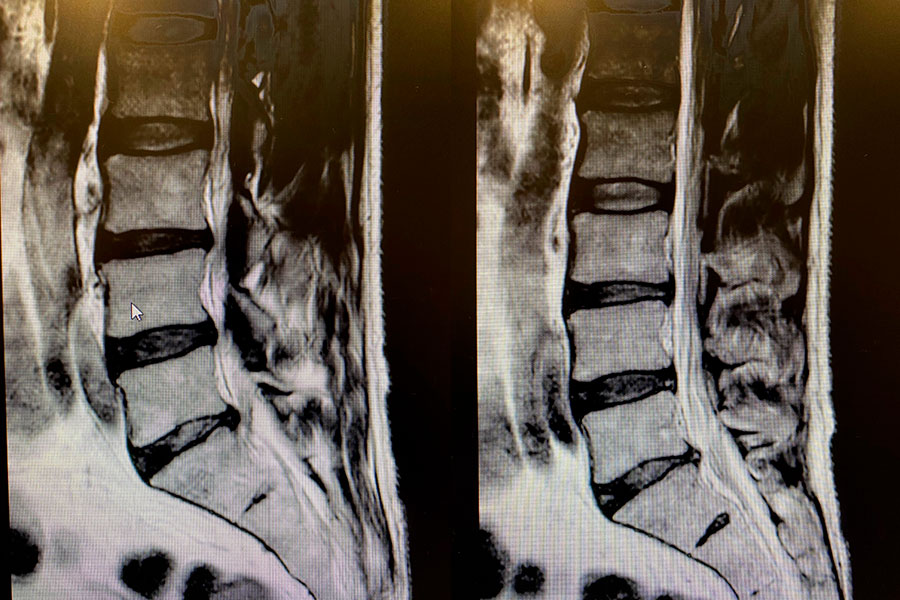

El paciente presenta una patología en el disco, con una hernia de gran tamaño. Esto comprime las raíces neurológicas, generando listesis.

La paciente acude con una hernia discal central, que produce estenosis de canal y síntomas compresivos que se extienden a lo largo de las piernas.

El paciente acude a consulta con una fuerte ciática y dolor irradiado hacia las piernas. Se diagnostica una hernia discal mononivel L5S1 con calcificación.

En este caso clínico nos encontramos ante un paciente de que sufre dolor lumbar por la aparición de una hernia entre la 4º y la 5º vértebra.

En este caso clínico nos encontramos ante un paciente de 33 años que aqueja dolor persistente que se alarga hasta la planta del pie.

Nos encontramos ante un paciente con dolor crónico agudo que presenta paréntesis en MMII en el territorio de L5.

Nos encontramos ante un paciente con 48 años de edad que padece de hernia discal izquierda compresiva, que le produce dolor en gran parte de su cuerpo.

Nos encontramos ante un paciente de unos 40 años, que acude a nosotros por un dolor intenso en la pierna derecha que le avanza hasta la planta del pie.